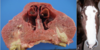

Fibrous osteodystrophy, "Rubber jaw"

Fibrous osteodystrophy

Fibrous osteodystrophy

Fibrous osteodystrophy